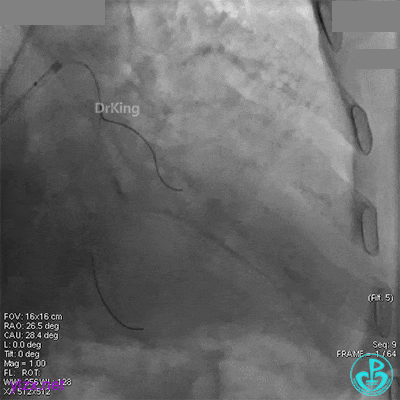

经刺破球囊冠脉内推注硝普钠后血流恢复2级,远端分支血管没有充分显影。

退出分支导丝后造影,血流不足3级。

术后心电图无明显改变。